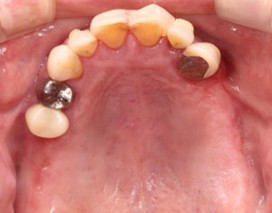

40代 女性

(薬・注射・レントゲン・CT・データ分析・骨造成・サージカルステント・血液検査) - 年齢/性別

- 40代/女性

- 患者の具体的な症状

- 左上6欠損のため義歯を使用していたが、噛むと痛みがあり不快なため、インプラント治療を希望

- 検査方法

- コーンビームCT、レントゲン撮影

- 診断結果

- 左下6欠損

- 治療詳細

- コーンビームCTによる画像診断で垂直的な骨高が不足し骨密度が少ないため、ソケットリフトによる骨再生治療とインプラント埋入を同時に行った。

- 通院回数

- 7回

- 治療期間

- 7か月